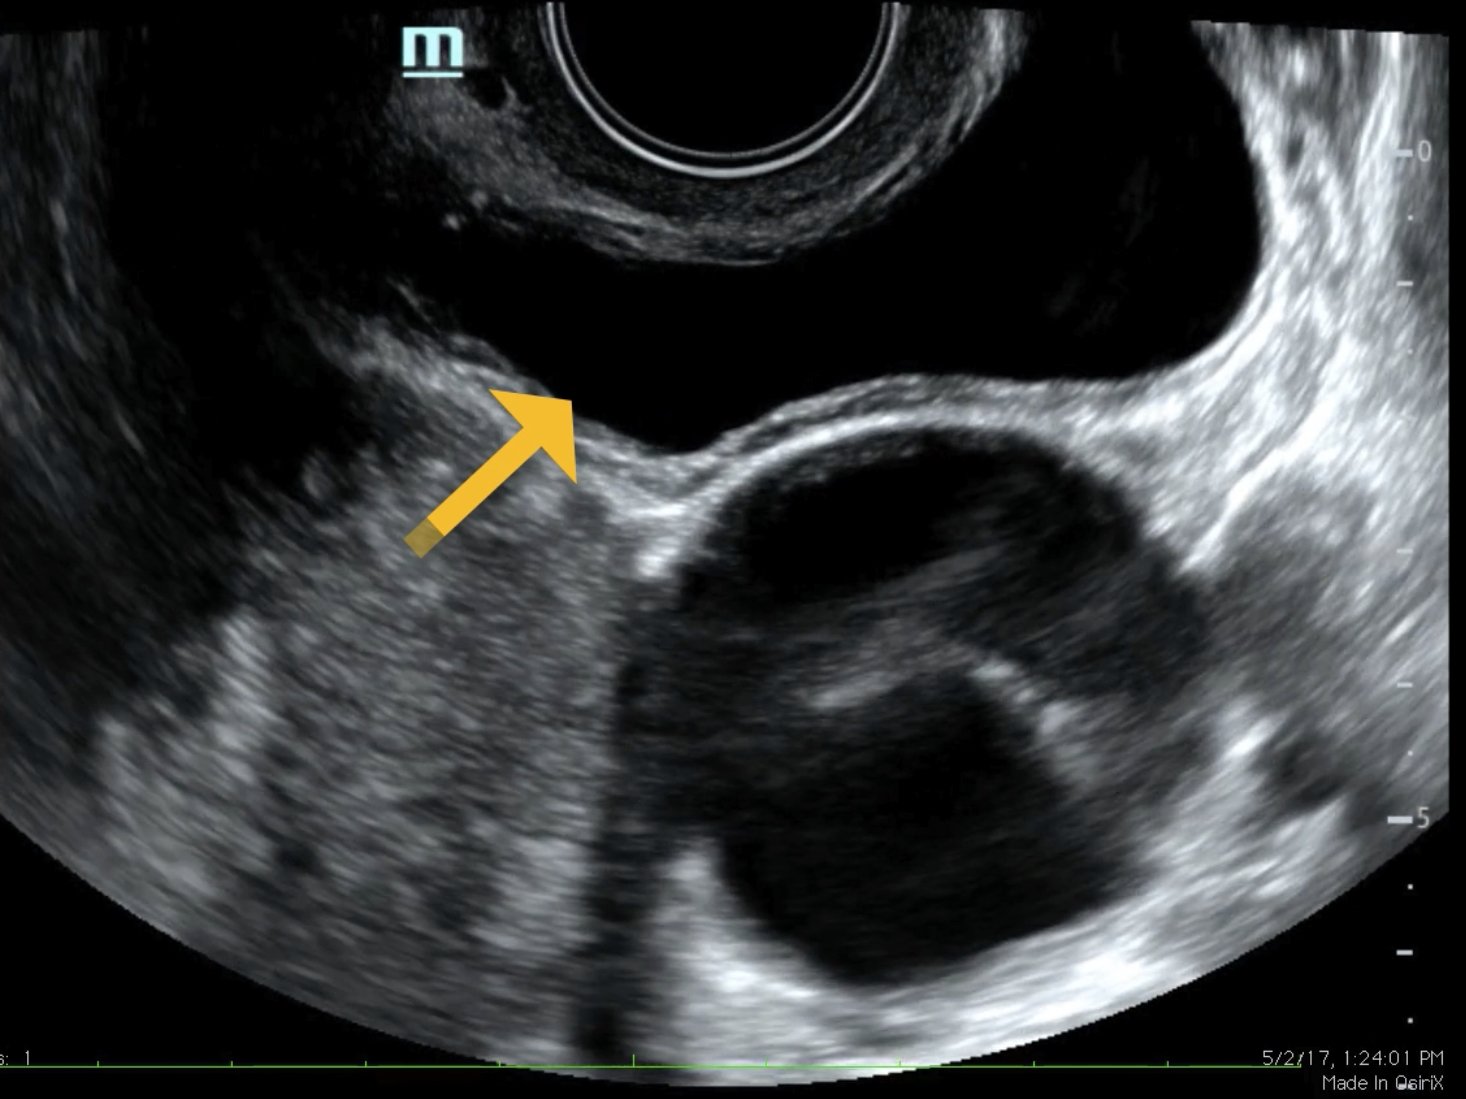

The ultrasound video clip demonstrates a transverse view of the pelvis using the endocavitary probe. The bladder can be seen on the anterior portion of the scan (yellow arrow), while the uterus with an intrauterine pregnancy is visible posteriorly (blue arrow). The thickened appearance of the uterine wall is also indicative of pregnancy. A large, anechoic cystic structure measuring approximately 5 cm is seen in the vicinity of the patient’s left adnexa (pink arrow), which raises concerns for ovarian torsion.1

Based on the clinical presentation and the bedside ultrasound, obstetrician-gynecologist (OB/gyn) was emergently consulted and the patient was transferred to the operating room (OR) where she was found to have a paratubal cyst in the left fallopian tube with associated isolated tubal torsion. After manually de-torsing the tube, which was initially dilated and dusky, blood flow was restored and the color returned to normal. A cystectomy was performed without complications. The patient was discharged later that day after the follow-up ultrasound showed reassuring fetal heart tones and good blood flow to the left ovary.